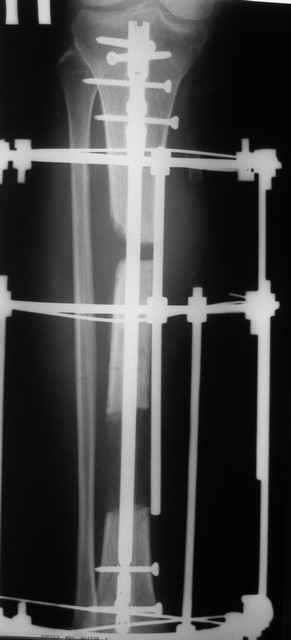

Тогда можно рассмотреть вопрос одновременного удаления штифта, мышечной (в данной области применим проксимально отсеченный лоскут камбаловидной мышцы) или микрохирургической (что более надежно) пластики дефекта мягких тканей, остеотомии проксимального фрагмента большеберцовой кости, остеосинтеза блокируемым штифтом с а/б покрытием, наложения простого аппарата Илизарова (можно из полуколец) для дистракции на штифте. При данном варианте пациент сохраняет возможность полной опоры на ногу, что очень важно для заживления у пожилого пациента) и отпадает необходимость в проведении дополнительный операций (при благоприятном развитии событий).

Выкладываю картинки похожей пациентки. Извините, что без окончательных снимков (сейчас их нет под рукой). Правда мы имели проблемы у данной больной после снятия аппарата, когда промежуточный фрагмент большеберцовой кости сместился на 1,5 см дистально и отошел от проксимальной части кости. До сих пор у пациентки на снимках определяется лишь тонкая полоска кости по задней поверхности за штифтом (образовалось что-то вроде маленького регенерата)в области стыковки промежуточного и проксимального фрагментов. Больная пока решила подождать. Не хочет оперироваться, так как ходит не хромая, работает.